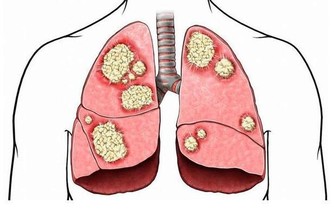

眼球突出伴怕熱多汗,留神甲亢

怕熱多汗是甲亢的特徵之一,此外還表現為身體消瘦、心率過快、精神緊張、難以入睡、大便次數增多等,嚴重時眼球出現突出。

一旦出現這些症狀應及時就醫,對症治療。保證碘攝入量是防止甲亢的主要措施,如適當攝入海帶、紫菜等含碘較多的食物。